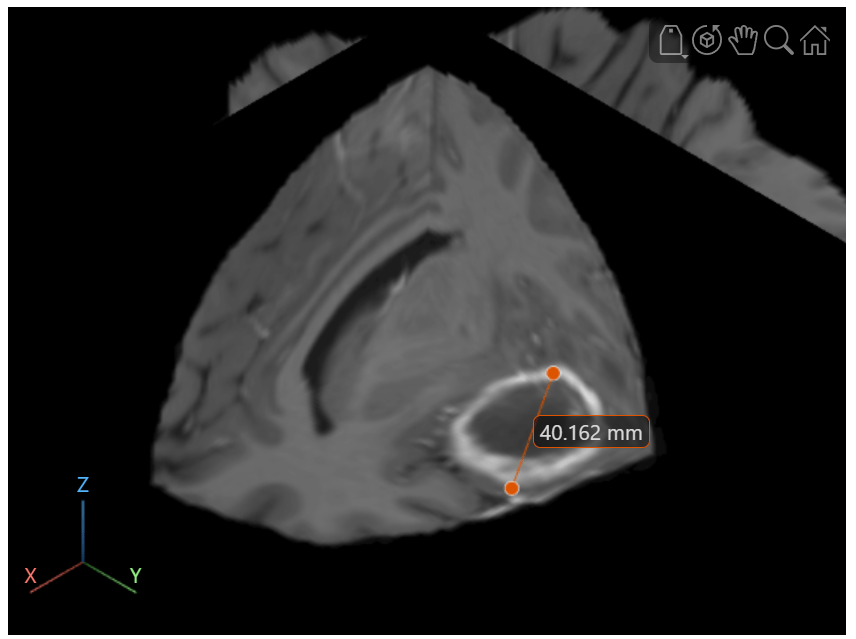

Load a 3-D MRI image volume, vol, with 1-by-1-by-1 mm voxel spacing into the workspace. The MRI data is a modified subset of the BraTS data set [1].

dataDir = fullfile(toolboxdir("images"),"imdata","BrainMRILabeled"); load(fullfile(dataDir,"images","vol_001.mat"))

Create a viewer to display the volume. By default, ROI annotations display in voxel units with no label. To display a units label, specify the SpatialUnits property of the viewer.

viewer = viewer3d;

viewer.SpatialUnits = "mm";Display the volume in the viewer as 2-D slice planes. Note that specifying the SpatialUnits property only changes the label units. If your volume has voxel spacing other than 1-by-1-by-1 mm, you must specify the Transformation argument of volshow to display the volume correctly and generate accurate measurements.

Volume = volshow(vol,Parent=viewer, ... RenderingStyle="SlicePlanes");

Add a line annotation to measure the tumor size using the uidraw function. To draw the line, first rotate the volume to view the transverse plane by clicking the Z axis indicator in the lower-left corner of the viewer. To facilitate accurate measurement, zoom in on the region containing the tumor. Click and hold the slice to place the first endpoint, drag to draw the line, and release to place the second endpoint.

line = uidraw(viewer,"line");Zoom in to focus on the tumor region.

viewer.CameraZoom = 3;

Optionally, to reposition one endpoint, drag the endpoint, not the line or the label. To move the whole line, including both endpoints, hold Ctrl and drag one of the endpoints.